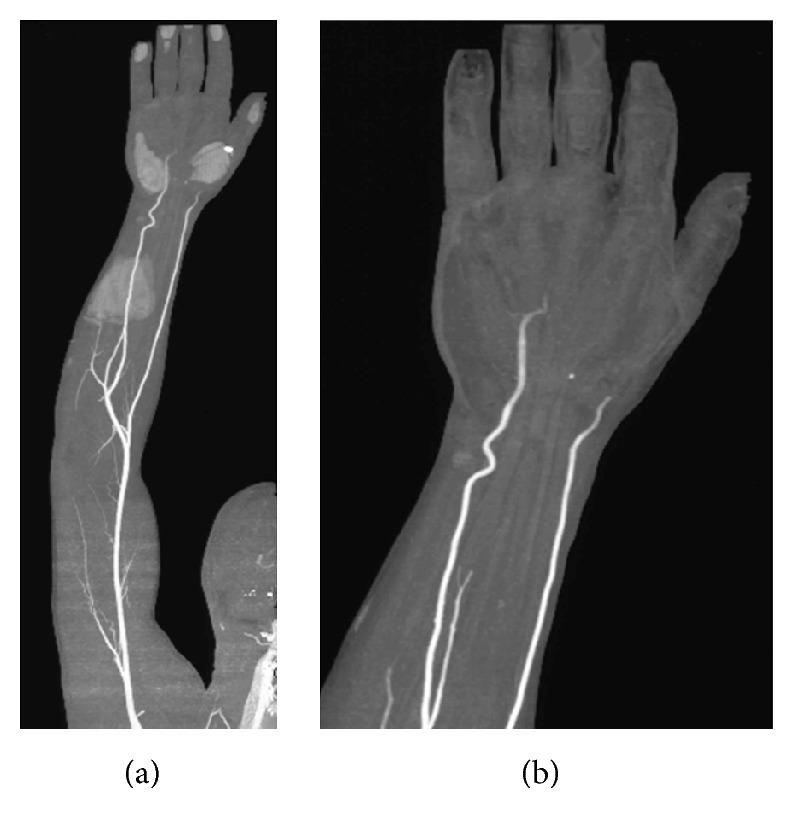

Thenar and hypothenar hammer syndromes are uncommon conditions characterised by digital ischemia of the hand as a result of repetitive trauma at level of the thenar and/or hypothenar eminence and damage to the radial and/or ulnar arteries, respectively. The symptoms are related to the mechanism of the trauma and a Raynaud's phenomenon can be predominant for a long time. The angiography is the "gold standard" imaging technique which allows to confirm the diagnosis. Therapeutic strategy depends on the type of the lesion and severity of symptoms and includes pharmacological (antithrombotic and thrombolytic drugs) and surgical treatments. The authors present a case of a 53-year-old man, carpenter by profession, with combined thenar and hypothenar hammer syndromes and Raynaud's phenomenon, successfully treated with a short course of intravenous infusion of iloprost.

大鱼际和小鱼际锤状指综合征是罕见病症,其特征是由于大鱼际和/或小鱼际隆起处反复创伤,分别导致手部指端缺血以及桡动脉和/或尺动脉损伤。症状与创伤机制有关,雷诺现象可能长期占主导。血管造影是“金标准”成像技术,可用于确诊。治疗策略取决于病变类型和症状严重程度,包括药物治疗(抗血栓和溶栓药物)及手术治疗。作者报告了一例53岁男性病例,职业为木匠,患有合并的大鱼际和小鱼际锤状指综合征及雷诺现象,通过短期静脉输注伊洛前列素成功治愈。